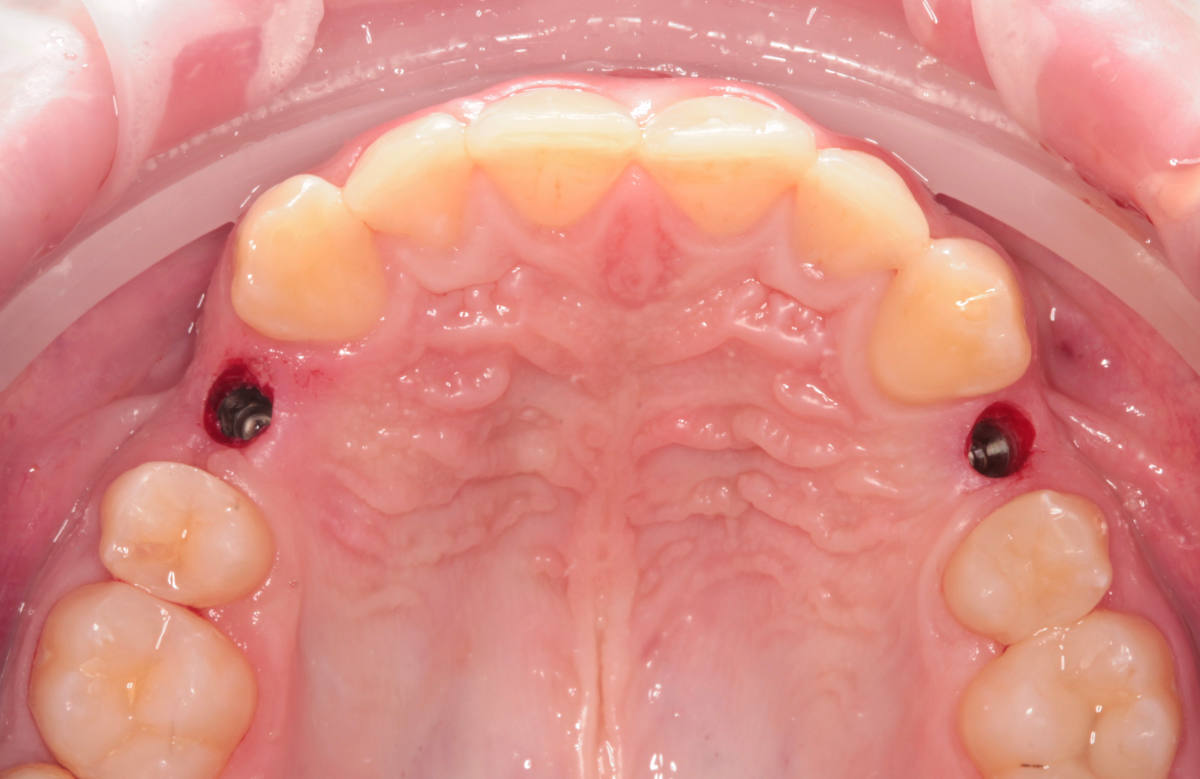

Navigovaná chirurgia, 3 implantátov

Autor práce Dr. Michal Repaši

Zubný technik Vasil Csopej